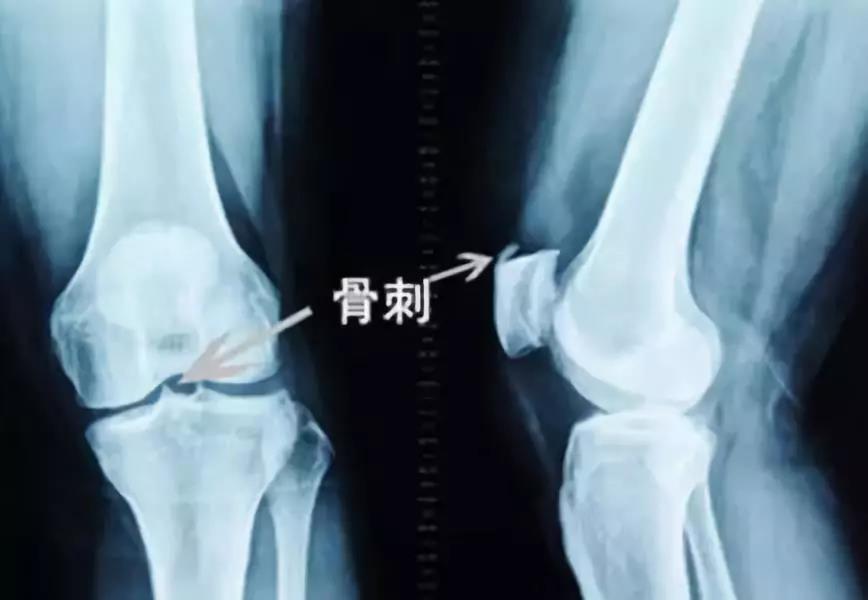

刘大爷纳闷:自己膝盖里面长了骨刺,经常锻炼,骨刺应该越磨越平?为什么反而越来越严重呢?

不过刘大爷看到检查报告单上写着“骨刺增生”的字样,医生还指着X片中阴影告诉他“就是这些刚长出来的骨刺”。

结果非但没有磨掉骨刺,反而骨刺越来越粗,就连剩余好的软骨也被磨掉了,膝盖疼痛难忍,不得不进行手术治疗。

湖南中医药大学第一附属医院卢敏教授解释:骨刺就是骨质增生,是由于肌肉、韧带的牵拉,关节劳累、磨损,日积月累逐渐形成的骨赘。